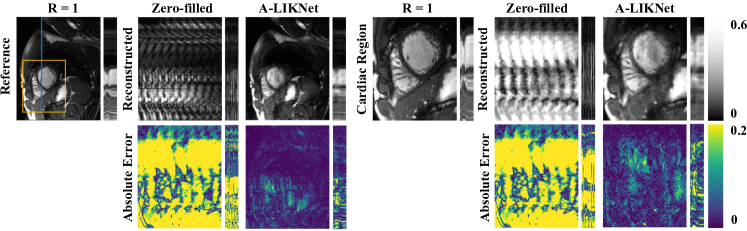

To investigate the generalization performance of different DL-based networks, we tested pre-trained networks on the prospectively real-time undersampled OCMR dataset [51]. It is important to note that the pre-trained networks were not fine-tuned on the OCMR dataset but were used directly for testing. Fig. 8 displays two 8×8\times undersampled short-axis slices and the reconstruction results of MoDL, KIKI-Net, L+S-Net, and the proposed A-LIKNet.

Refer to caption

Figure 8: Reconstructions in spatial (x-y) plane of the proposed A-LIKNet in comparison to zero-filled, MoDL, KIKI-Net, and L+S-Net for a healthy subject who was prospectively undersampled with VISTA sampling (R=8). Two different slices are shown on the right and left sides. The second row shows the enlarged views of the cardiac region (yellow box region).

In general, all four deep learning networks can reconstruct the prospectively undersampled images with high quality. Although the differences are subtle, A-LIKNet performs slightly better than the other methods. In both the full-view and magnified cardiac region images, we can observe that MoDL, KIKI-Net, and L+S-Net still exhibit some residual stripe artifacts (indicated by yellow arrows). Additionally, the reconstructed images of A-LIKNet display better contrast.